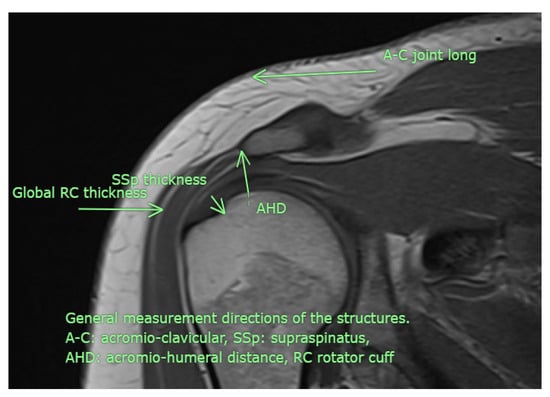

All USG evaluations were performed by a physical medicine and rehabilitation specialist with +30 years of experience in musculoskeletal USG using a GE LogiqP6 Pro device GE Ultrasound Korea, Gyeonggi, Republic of Korea and a linear transducer. Imaging was performed using standard shoulder sections while the patients were in a sitting position with an elbow flexed and an arm internally rotated and laid on the anterior thigh. We laid the probe on the coronal plane on the acromio-clavicular joint. We then moved it laterally to detect acromial-end and subacromial structures, including the subacromial bursa (SB), rotator cuff, and humeral head. Beneath the SB is the supraspinatus tendon (SSp), which attaches to the tuberculum majus of the humerus. The arm was rotated and abducted to examine the tendinous integrity and motion of the SSp. To measure the AHD and ensure standardization, a perpendicular line was drawn from the most lateral tip of the acromion to the head of the humerus, yielding an automatic value via USG-software vR2.0.5 (Figure 2 and Figure 3). In this position, we evaluated the supraspinatus and RC and measured their thicknesses on the short axis. The thickness of the SB was noted. Then, the probe was retracted, and the internal structure of the infraspinatus (Isp) and its thickness were measured. Notably, the teres minor, though difficult to discriminate, is at the posterior end of the ISp. Then, the probe was moved to the short axis to examine the biceps tendon. Here, the probe was turned to the longitudinal axis to evaluate the long biceps tendon and determine its thickness. The probe was then moved to the back side on the short axis to examine the labrum, glenoid bone, humeral head, and joint capsule. If the probe is turned longitudinally, the muscle bellies and myo-tendinous junctions of the RC muscles can be seen. Subsequently, the arm was externally rotated, and the probe was again placed medial to the biceps tendon to expose the tuberculum minus, subscapularis tendon, and anterior acromion, along with the coracoacromial ligament. Then, we positioned the arm posteriorly on the back pocket. The measurements regarding the SSp, Isp, and RC were repeated and recorded. During the examination, the acromioclavicular joint, RC tendons (supraspinatus, infraspinatus, subscapularis, and teres minor), long-head biceps tendon, SB, and related structures were evaluated in all planes. Tendon thickness, the presence of subacromial effusion, ruptures, tendinous degeneration, contour irregularities, RC integrity, and homogeneity were examined. Measurements were performed before (baseline) and after the treatment (post-tr).

Figure 3. Although examined in all available directions, this MRI image illustrates the measurement sites used in the study (personal archive).